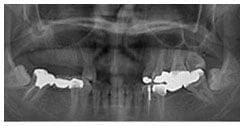

X 光片

術前X光片